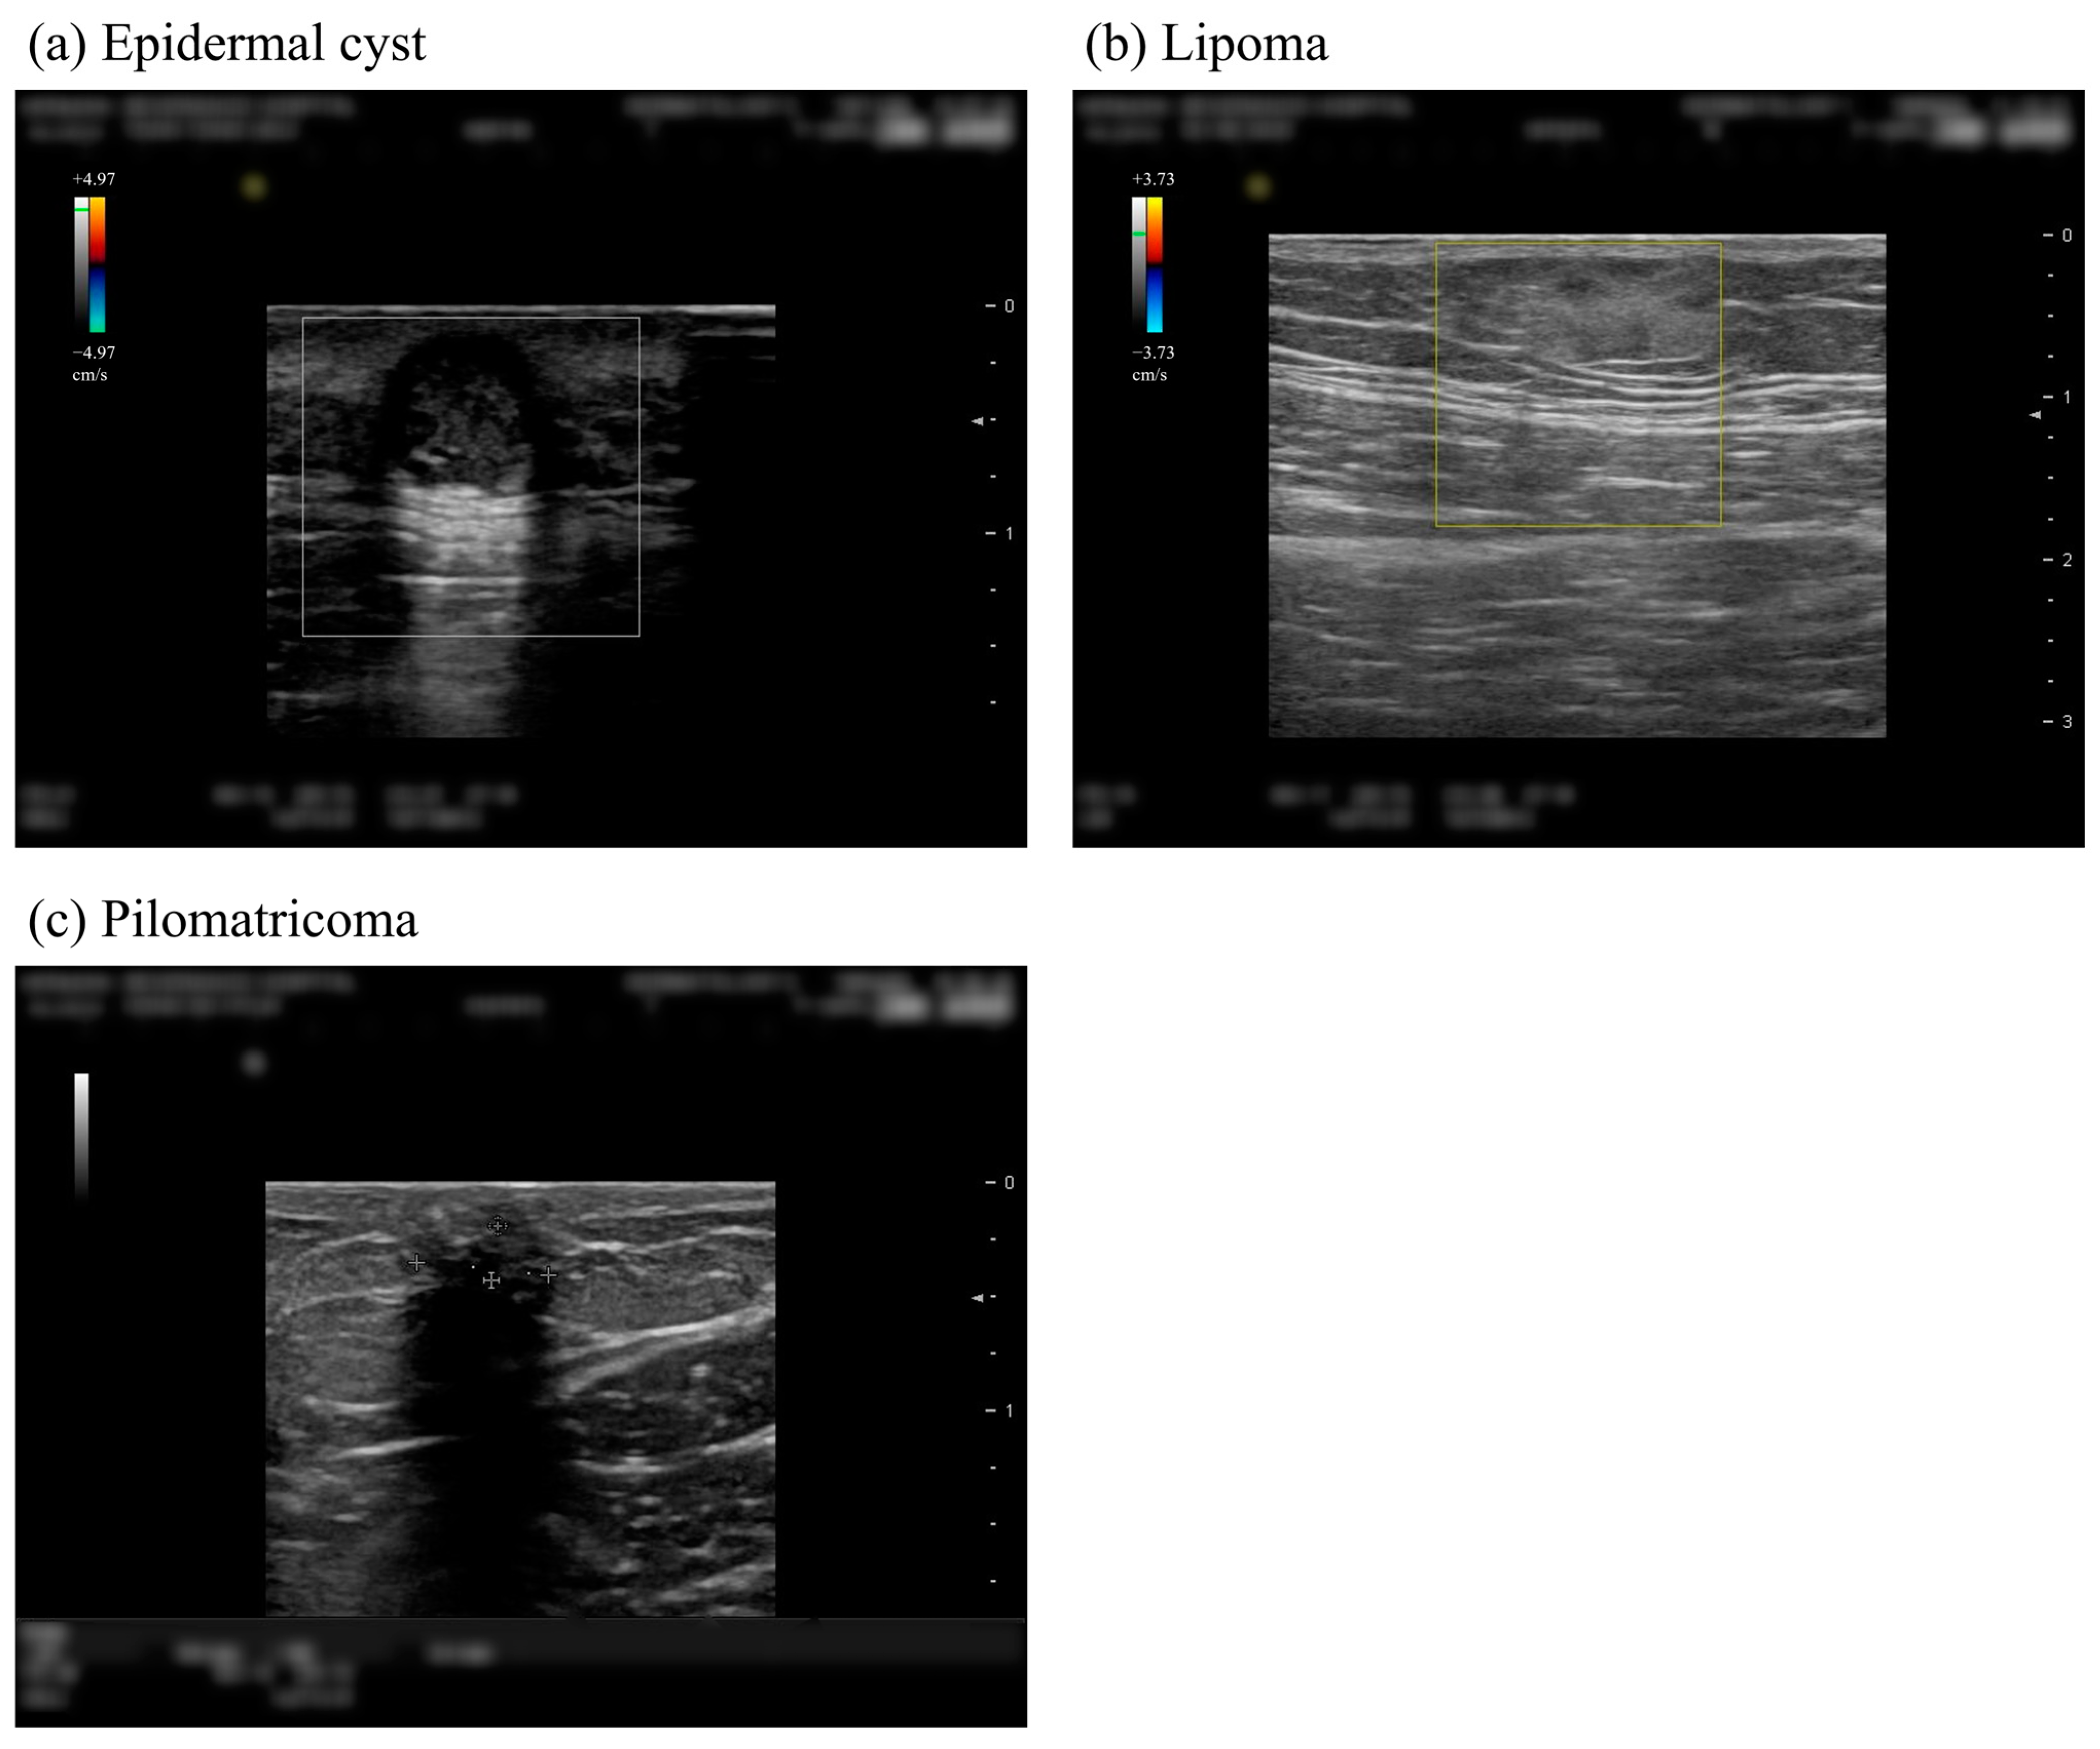

:1. Introduction

2.1. Study Subjects

2.2. Data Preprocessing